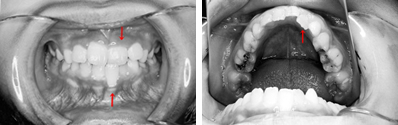

前歯の反対咬合と、それに合せて歯肉が下がっていることが心配されました。下顎の凸凹も問題でした。

上顎左側の2番目の永久歯(側切歯)が反対咬合です。まだ乳歯も多く残る歯並びですが、全体に凸凹が認められます。